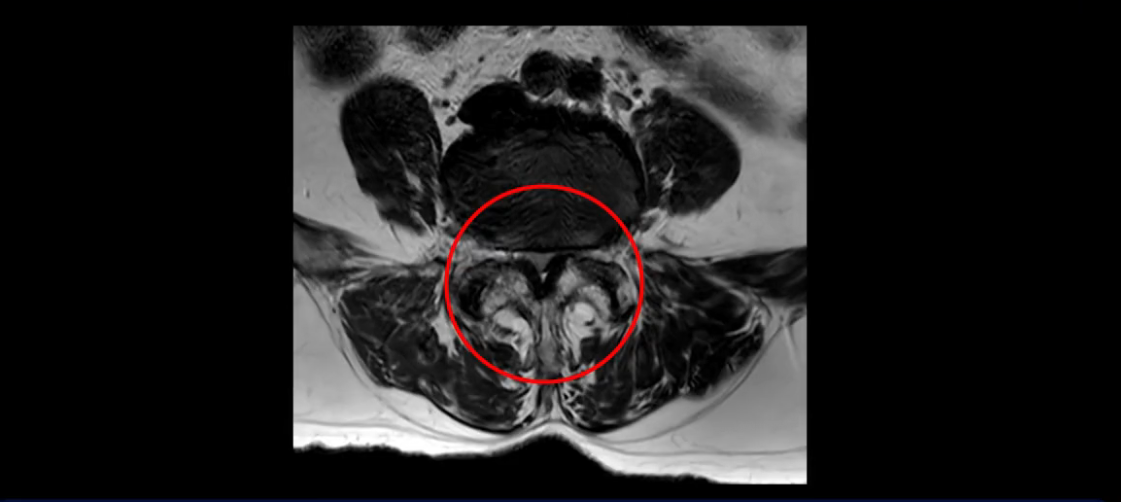

이분 MRI 보시면 허리 3마디의 퇴행이 매우 심합니다.

또 척추관협착도 매우 심합니다.

척추관이 심하게 좁아져 있습니다.

이렇게 여러 마디가 안 좋고 뼈도 밀려 나가 있으니까 나사박는 수술해야 하는데, 대학병원에서도 수술을 한 번에 못 하고 두 번에 나눠서 해야 한다고 들으셨습니다. 왼쪽으로 신경가지가 빠져나가는 추간공도 많이 좁아져 있습니다.

이렇게 신경 구멍들이 좁아져 있고 신경이 눌리니까 엉덩이와 다리가 너무 저리고 아파서 아예 일어서질 못하니까 휠체어를 타고 병원에 내원하셨는데요. 그럼 어떻게 이분처럼 신경이 눌려있는 환자분들을 수술 없이 치료해서 잘 걷게 만들고 엉덩이와 다리가 저리고 아픈 증상이 사라지게 할까요? 지금부터 설명해 드립니다.